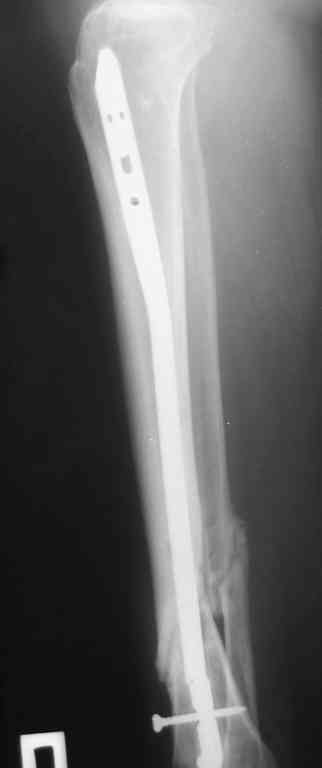

Re: Ложный сустав голени перелом штифта

послал В. Машталов 23 Октябрь 2007, 12:09

Прилагаются.